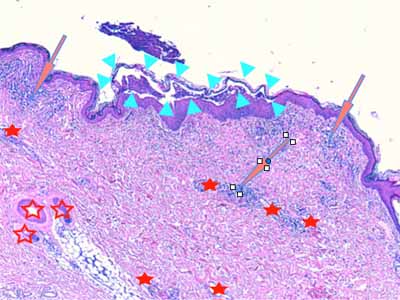

Photo 8 (Hémalun Eosine X 40) : L’épiderme est parsemé de vésiculo-pustules sous-cornées,

extensives, planes, dont le toit, composé de fines lamelles de kératine orthokératosique, est fragile.

Le derme montre un infiltrat de topographie péri-vasculaire.

Le patron lésionnel est celui d’une dermatite psutuleuse sous-cornée périvasculaire.

Légendes de la Photo 8 :

- Pointe de flèche turquoise : pustule intra-épidermique sous-cornée

- Flèche orange : infiltrat dermique de topographie péri-vasculaire

- Étoiles rouges pleines : vaisseaux sanguins

- Étoiles rouges vides : follicules pileux